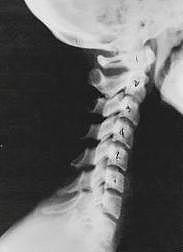

Phase Three Subluxation Degeneration is caused by subluxations that have been continuing on for between 40 and 65 years. This phase has all of the attributes of the previous phases, only worse. The curvatures are abnormal, the disc spaces are vastly decreased and changed. Calcium changes on the spine are abundant in this phase. Normally, people in phase three have a restricted range of motion and probably exhibit symptoms of some kind. In phase three the vertebrae show obvious changes and mutations in shape. Projections made of calcium, sometimes referred to as "spurs or lipping", can be readily seen on x-ray. Chiropractic reconstructive care for patients in phase three ranges from 2.5 years to 3.5 years. This does not mean that at the end of this time that any or all of the calcium changes will be gone. In many instances the body adapts to the presence of the calcium and positive changes can only be measured from a functional standpoint. As before, if Phase Three Subluxation Degeneration is left unchecked it slowly advances onward into the next phase.

Phase four subluxation degeneration is seen with subluxations that have been raging on uncorrected or altered for over sixty five years. Phase four is a grave condition that will negatively affect the patients longevity and quality of life. The massive amount of neurological damage caused by years of subluxation that have lead to phase four are probably taking a serious toll on this person's health status. X-rays in phase four show serious severe structural changes. Vertebrae exhibit massive calcium changes, disc spaces appear blurred, and the bones themselves appear fused. In this scenario the patient will have a severe restriction of range of motion in addition to probably a number of other health issues. Reconstruction may not be possible in phase four, but care can be directed to some reduction in subluxation with the goal of improvement in the quality of life remaining. Patients in Phase Four Subluxation Degeneration have a serious situation both structurally and neurologically, but they are certainly not beyond hope. Many patients in phase four report significant improvements in symptoms, conditions, mobility and quality of life.